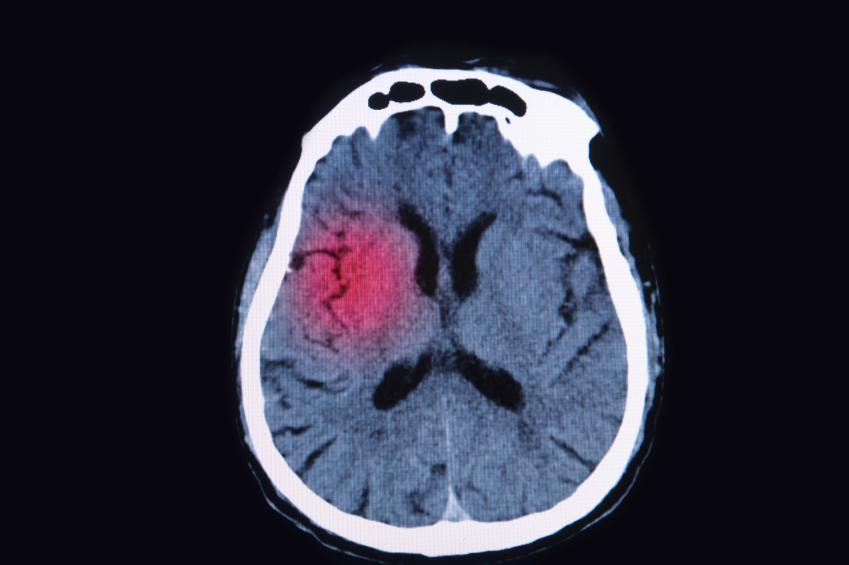

Aneurisma cerebral

Tipo de dor: fisgadas fortes na cabeça

Pontadas na cabeça ou fisgadas podem ser um dos sintomas dessa condição que é caracterizada por uma dilatação anormal de uma artéria no cérebro mas nem sempre apresenta sinais. Além da dor de cabeça forte, pode haver também problemas de visão, rigidez no pescoço, dificuldade para falar e se orientar, convulsões e perda de consciência.

Causas de aneurisma cerebral

- Genética;

- Golpe na cabeça;

- Lesões cerebrais;

- Abuso de substâncias ilícitas.

Tratamento para aneurisma cerebral

Um aneurisma é um problema sério e urgente que deve ser acompanhado por um médico, sendo que em grande parte das vezes é necessário intervenção cirúrgica. Além disso, é imprescindível o controle da pressão arterial e níveis de colesterol, assim como hábitos saudáveis.

Tumor cerebral

Tipo de dor: pontadas na cabeça

Apesar de não ser a causa mais comuns, câncer no cérebro pode provocar dor de cabeça intensa e pontadas que costumam vir acompanhadas de outros sintomas constantes: